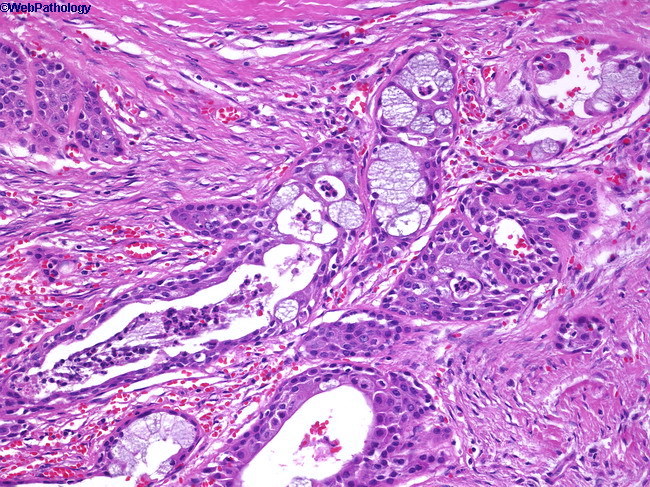

A 53 year old man presents with a mass in the parotid gland. You biopsy it and diagnose him with the second most common salivary gland tumor. What did you see on biopsy?

He has a Warthin tumor. This is characterized by a benign cystic tumor with abundant lymphocytes and germinal centers (like a lymph node).